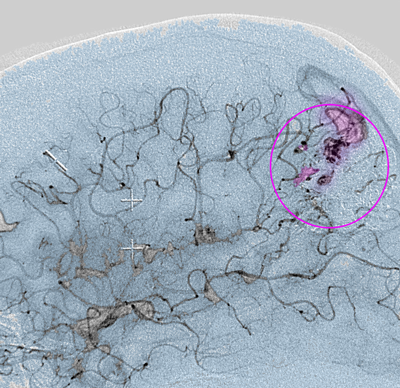

AVM2

Αρτηριοφλεβώδης δυσπλασία (περίγραμμα).